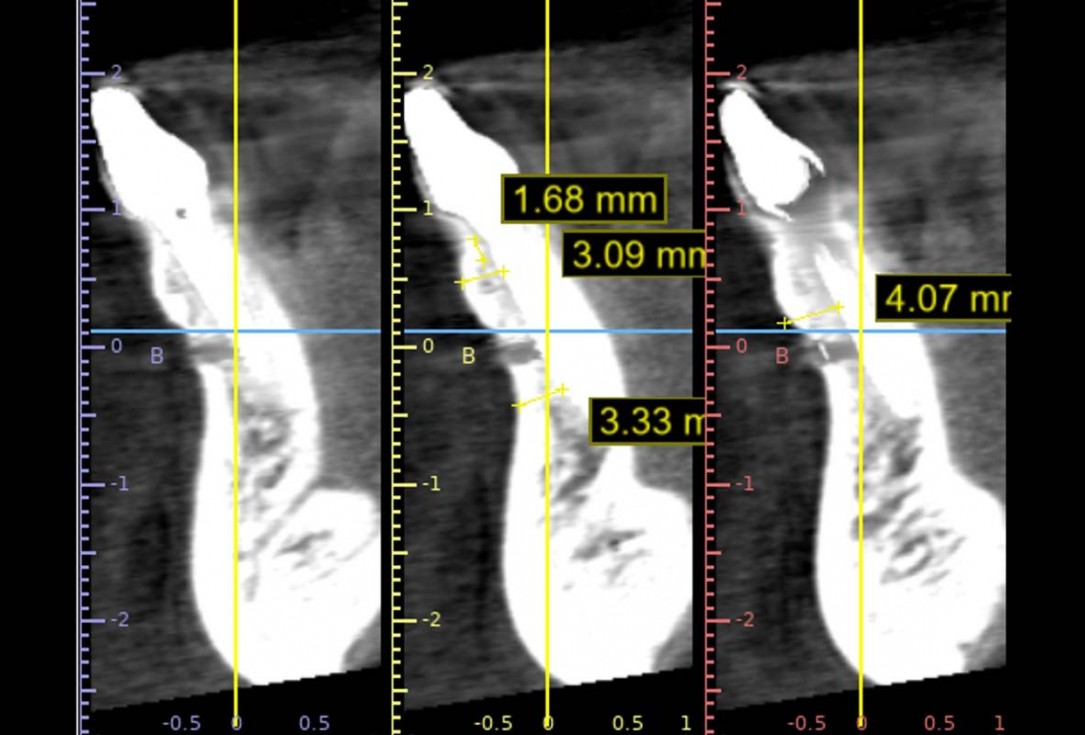

X-ray control before tooth extraction

Pre-operative x-ray image, teeth 43, 44, 45, 46 and 47 planned for extraction

Pre-operative OPG, teeth 24, 25, and 26 planned for extraction